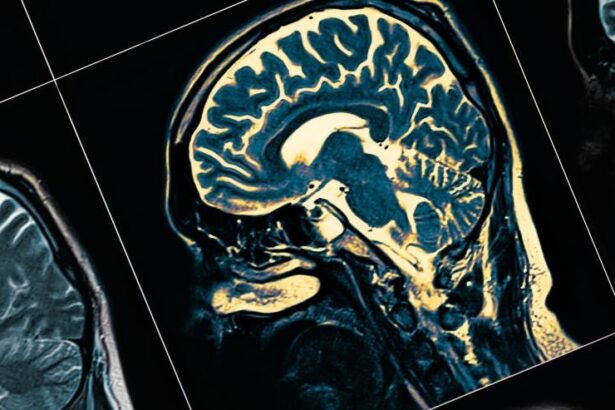

Cô Amie Skilton ở Úc mắc chứng sa sút trí tuệ Alzheimer do nhạy cảm với nấm mốc. Ảnh minh họa: SHUTTERSTOCK.

Bác sĩ xác định cô Skilton mắc chứng sa sút trí tuệ Alzheimer loại ba. Đây là dạng Alzheimer do tiếp xúc trực tiếp với một chất độc nào đó, thường là qua đường hô hấp. Chất độc sẽ gây phản ứng viêm mạn tính ở vỏ não, dẫn đến Alzheimer.